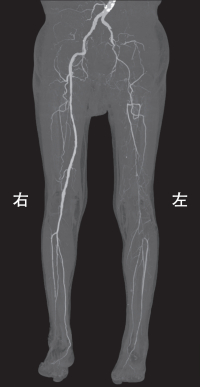

身長168 cm、体重 72 kg。脈拍 72/分、整。血圧 158/88 mmHg。胸腹部に異常を認めない。左膝窩動脈と左足背動脈の拍動を触知しない。下肢の三次元 CT 血管撮影像〈3D-CTA〉を別に示す。

c. 「左膝までの血流は良好に保たれています」